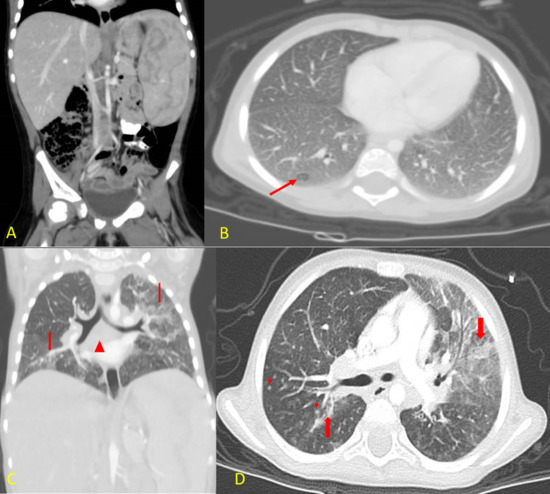

A few weeks later, she presented repeatedly with recurrent chest infections requiring hospitalization, which were believed to be secondary to recurrent aspiration. She underwent fundoplication with no improvement. She underwent bronchoscopy, and the lavage was negative for acid-fast bacilli. In addition, a PCR and culture for Mycobacterium were negative. Her chest CT showed patchy areas of consolidation and ground-glass opacities seen in both lungs, predominantly in the left upper lobe. Multiple innumerable nodules scattered in both lungs and multiple enlarged lymph nodes in the retro-tracheal, bilateral paratracheal, hilar, and subcarinal were also noted (Figure 5).

Figure 5. Patient’s CT scans in both coronal (A,C) and axial (B,D) views. (A) Contrasted CT scan of the abdomen and pelvis showing hepatosplenomegaly. (B) Axial lung window settings for lung bases demonstrating diffuse ground-glass opacity of both lung fields with diffuse smooth interstitial thickening and mosaic pattern of lung attenuation (arrow). (C) Coronal CT reconstruction demonstrating again the areas of consolidation, ground-glass opacity, and smooth interstitial thickening in both lung fields (thick arrows). The mediastinal lymphadenopathy, especially in the subcarinal region (arrowhead). (D) Axial CT scan of the chest with IV contrast lung window settings demonstrating multiple areas of consolidations (thick arrows) with surrounding ground-glass opacity, which were more prominent in the left upper lung lobe. There is also diffuse smooth interstitial thickening, and multiple small intraparenchymal lung nodules can be seen (short arrows).